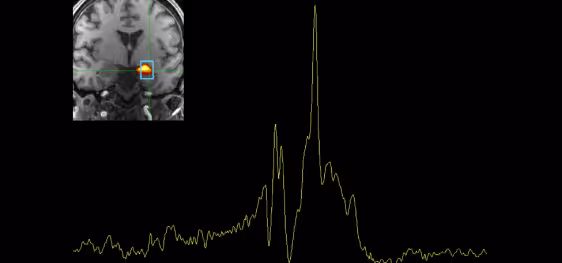

The Hurd Lab uses state-of-the-art technology to analyze human and animal tissues. Additionally, we use non-invasive neuroimaging techniques such as PET, MRS, fMRI, and small animal MRI to determine real-time changes in neural activity, neurotransmitter levels, and drug distribution, as well as structural changes in the brain. We pioneered DREADD-assisted metabolic mapping (DREAMM), a technique combining molecular pharmacogenetic and in vivo imaging strategies to provide high-resolution quantitative mapping of functional brain circuits associated with disturbance of genes expressed in specific cell populations.